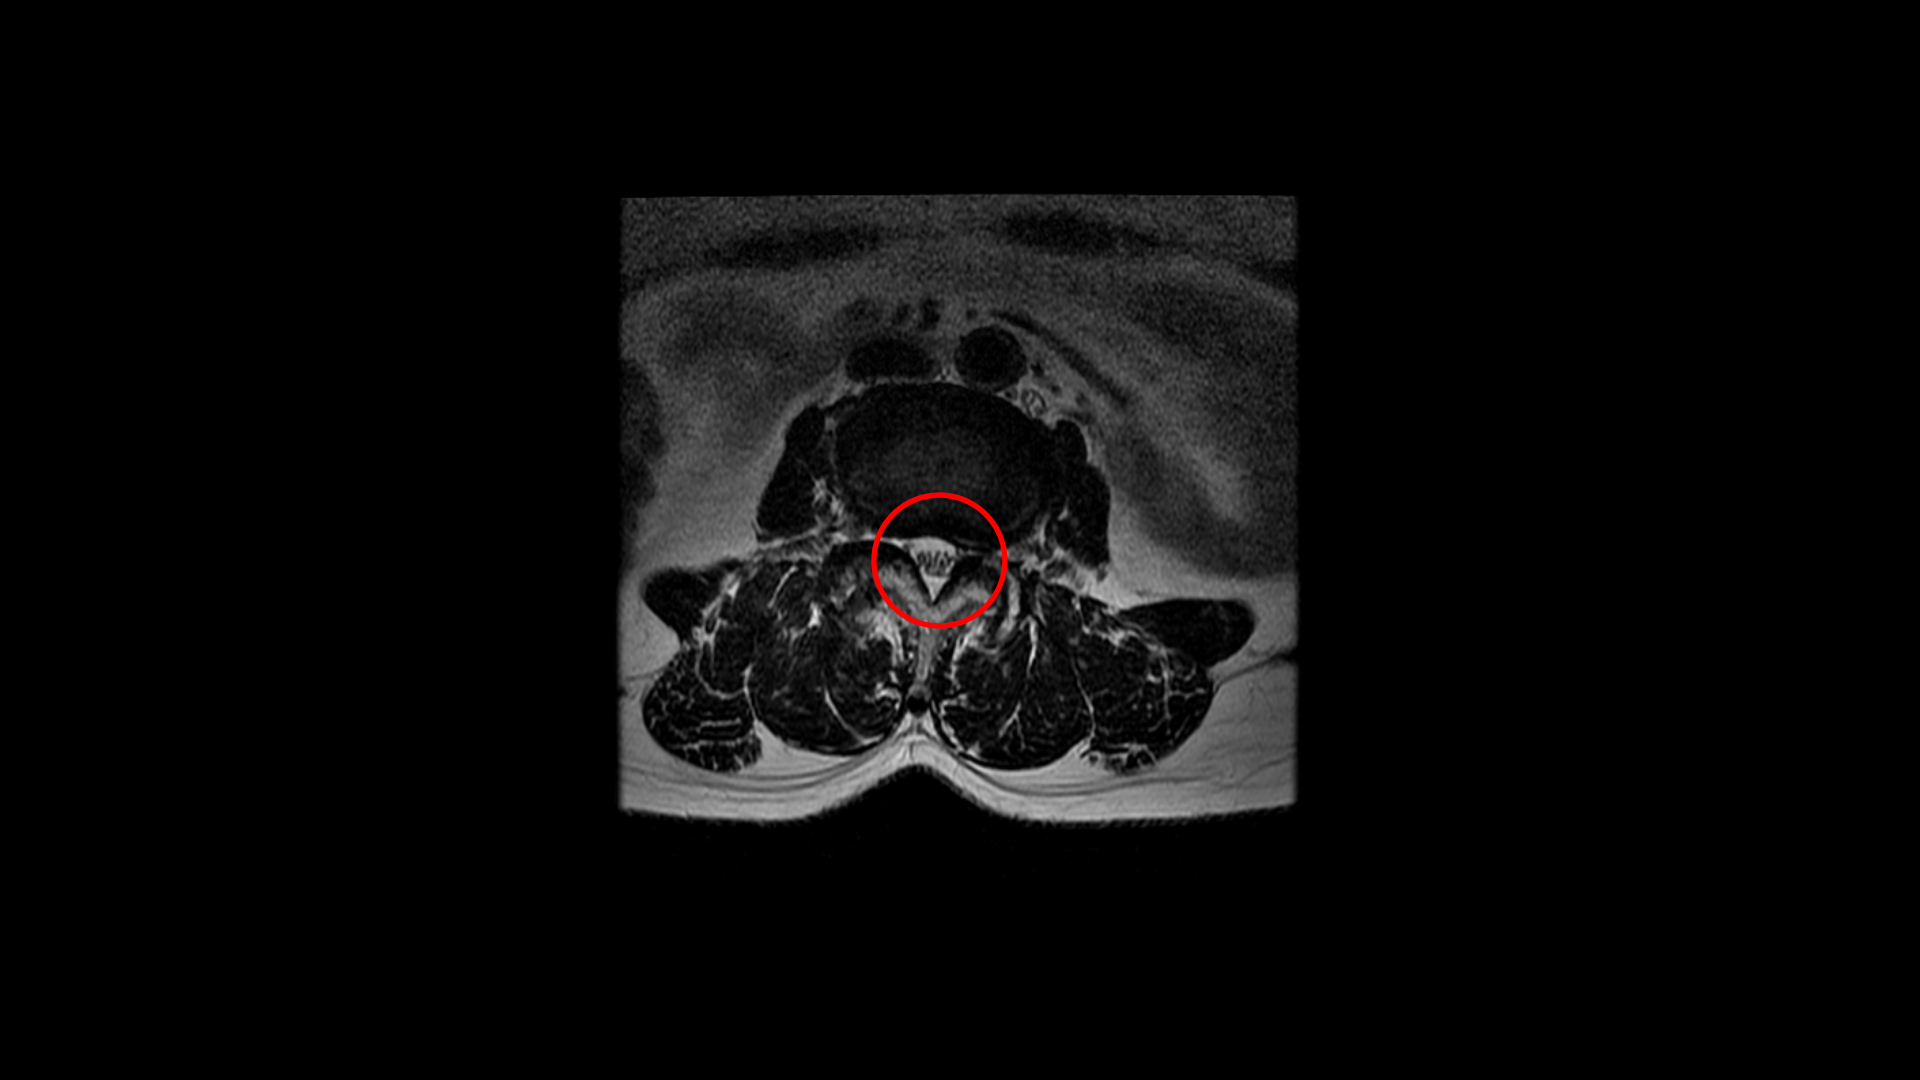

우선 이 환자분의 MRI를 함께 보겠습니다. 이 환자분의 척추에는 3번 4번과 4번 5번에 각각 1단계의 전방전위증이 있습니다.

중심성 협착도 있습니다.

그리고 중심성 협착도 있습니다.

그런데 이 환자분의 제일 불편한 증상은 왼쪽이 아니고 오른쪽 엉치와 다리 증상입니다. 이분 오른쪽 신경 구멍들을 보면 전부 다 넓게 잘 열려 있습니다.

엉치와 다리 방사통을 일으킬만한 특별한 신경 눌림이 보이지 않는 것입니다. 그럼에도 불구하고 여러 마디의 전방전위증과 척추관 협착 그리고 디스크 탈출이 있으니까 그것을 원인으로 보고 신경 주사도 맞고 시술도 받으셨습니다. 그러나 별 효과는 없었습니다. 그리고 대학병원에서도 결국은 수술밖에 방법이 없다고 수술을 권유하였습니다.

이 환자분은 MRI에서 오른쪽에 신경 눌림이 심해 보이지 않는 상태에서 오른쪽에 심한 방사통과 함께 오른쪽 중둔근이 극심하게 뭉쳐있는 것이 확인되었습니다. 만일 이 근육들을 풀어서 하룻밤 사이에 방사통이 사라진다면 그건 명확히 근육성 방사통이었던 겁니다. 보통 단단하게 뭉쳐있는 근육에 의한 방사통이라해도 하루만에 치료가 되는 경우는 매우 드뭅니다. 특히 7년씩이나 방사통이 있었으면 근육이 뭉쳐도 정말 심하게 뭉쳐있을 거고 엉덩이 근육만이 아니라 허리 근육 및 다리 근육들도 다 뭉쳐있을 가능성이 높기 때문에 1-2주 정도 매일 4-5회 이상 다양한 방법으로 근육을 풀어주면서 쉬는 걸 반복하는, 즉 풀어주고 쉬고 풀어주고 쉬고 풀어주고 쉬고를 반복해야 극심하게 뭉친 근육이 풀립니다. 그래야 방사통이 사라지고 좋아지는 겁니다.